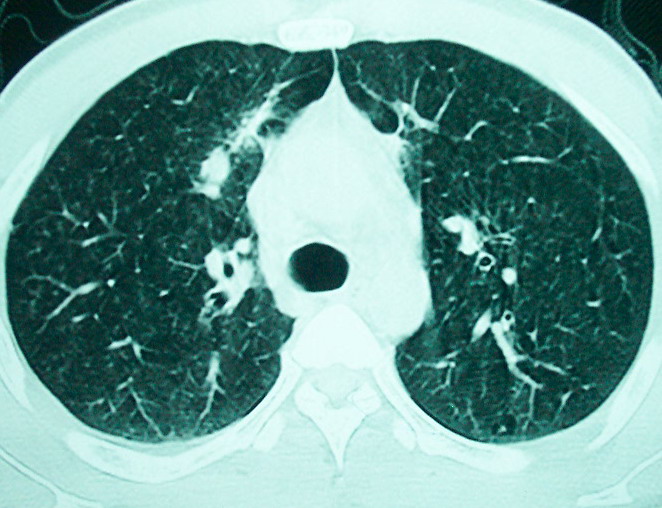

m      37y      发热   咳脓痰月余      ct肺脓肿但住院抗炎治疗后双肺内结节不知该如何解释

治疗后见左肺下野病灶较前缩小但双肺内结节影似无变化请较各位老师该如何下结论    治疗前wbc14.5 治疗后wbc 11.0

血源性肺脓肿,一般由原发感染灶引起脓毒败血症,在肺部形成小脓肿,病变变化快,容易形成肺气囊,脓气胸,主要与转移瘤鉴别,通过临床病史可分

结合临床发热,咳痰考虑为血源性肺脓肿,不过双肺结节又在肺的边缘,还是小心一点,抗炎后复查吧

除了肺内多发结节和左肺下叶的浓疡病灶,还应注意满肺散在的小结节影,还有右上肺前段支气管内膜不光整这些细节,结合病史,肺内多发结节应考虑结核性肉芽!

如果你仔细的同层面对比,你会发现所有的病灶均有比较明显的吸收、缩小。病变的形态,特别是脓肿的形态、壁的厚薄、内壁均有很大的变化,均在往好的方面发展。与临床症状、血像均符合,治疗效果比较显著,就是肺脓肿并双肺的化脓性炎症灶。